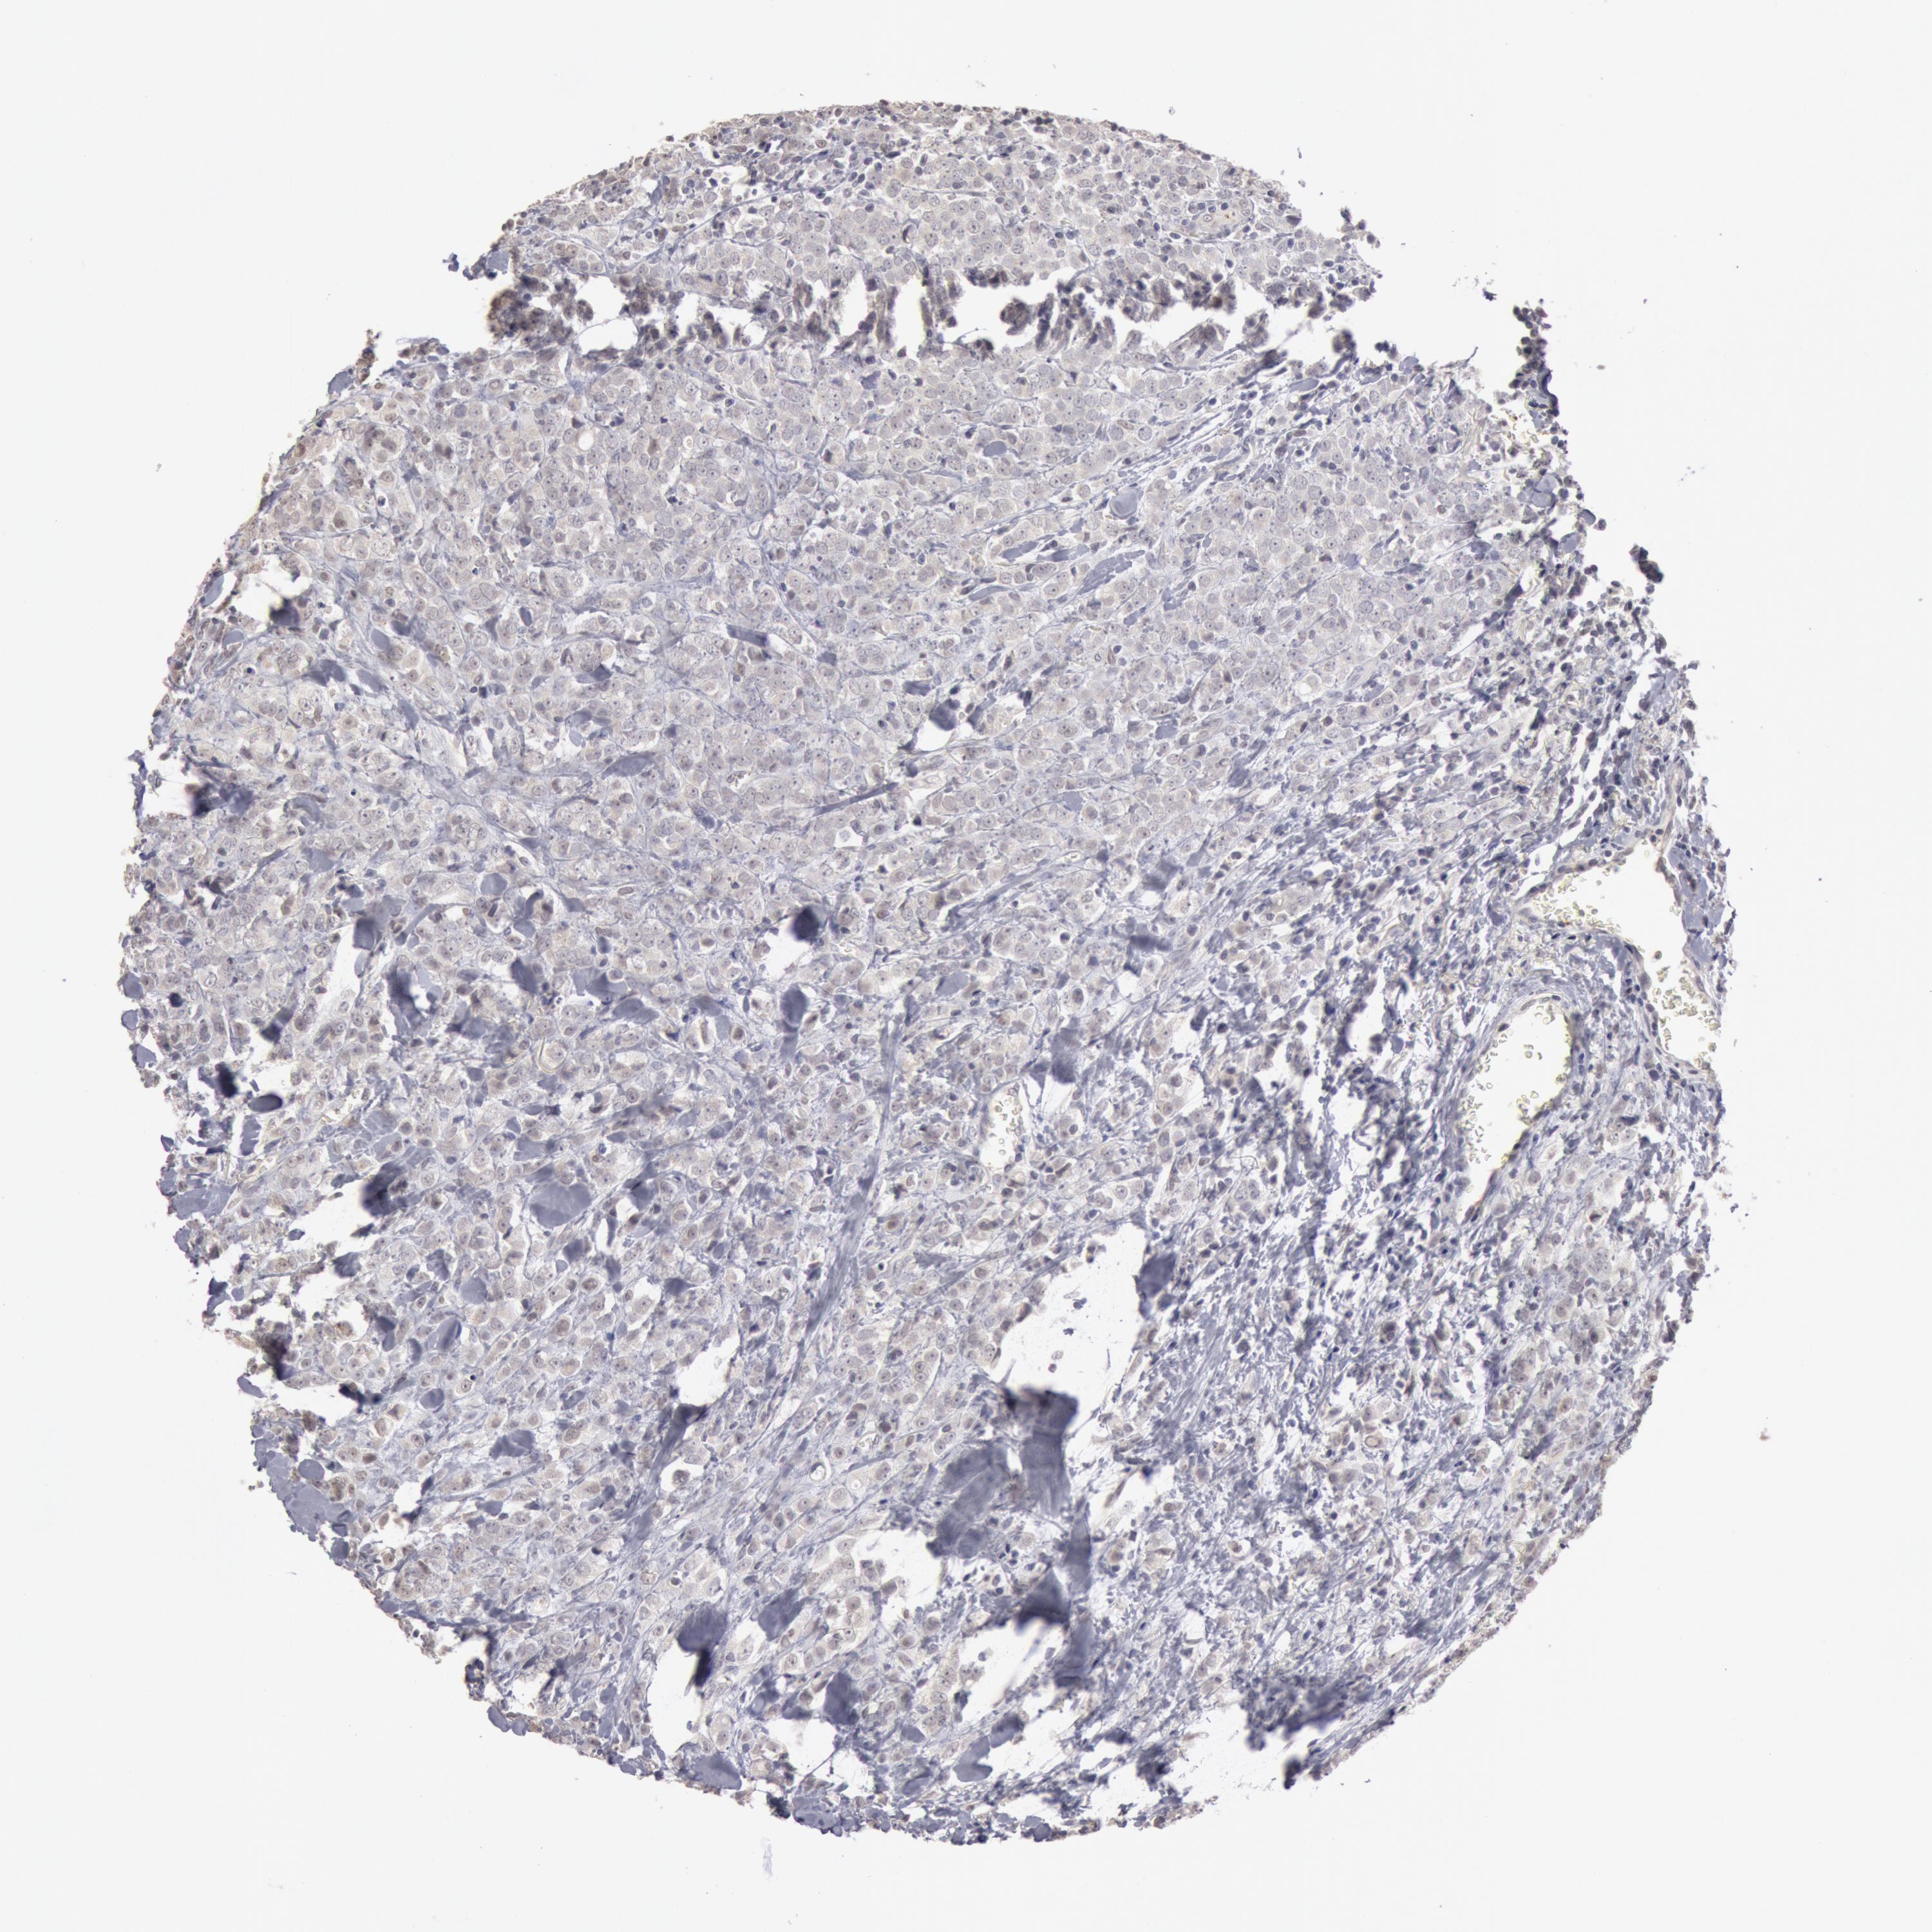

BRCA TCGA BRCA VALIDATION PROTEIN EXPRESSION

Breast cancer

Human cancer